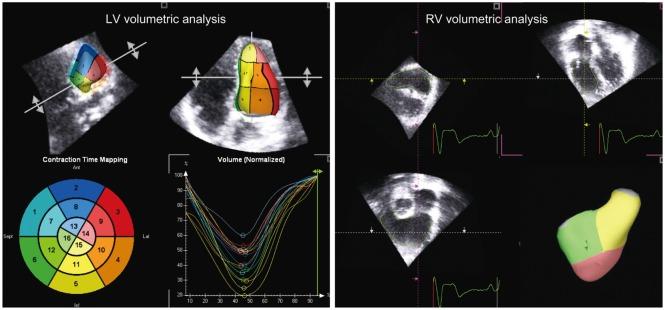

Significant improvement in survival of children with congenital cardiac malformations has resulted in an increasing population of adolescent and adult patients with congenital heart disease. Of the long-term cardiac problems, ventricular dysfunction remains an important issue of concern. Despite corrective or palliative repair of congenital heart lesions, the right ventricle, which may be the subpulmonary or systemic ventricular chamber, and the functional single ventricle are particularly vulnerable to functional impairment. Regular assessment of cardiac function constitutes an important aspect in the long-term follow up of patients with congenital heart disease. Echocardiography remains the most useful imaging modality for longitudinal monitoring of cardiac function. Conventional echocardiographic assessment has focused primarily on quantification of changes in ventricular size and blood flow velocities during the cardiac cycles. Advances in echocardiographic technologies including tissue Doppler imaging and speckle tracking echocardiography have enabled direct interrogation of myocardial deformation. In this review, the issues of ventricular dysfunction in congenital heart disease, conventional echocardiographic and novel myocardial deformation imaging techniques, and clinical applications of these techniques in the functional assessment of congenital heart disease are discussed.

先天性心脏畸形患儿生存率的显著提高,使得先天性心脏病的青少年和成年患者群体不断增加。在长期的心脏问题中,心室功能障碍仍然是一个重要的关注点。尽管对先天性心脏病变进行了矫正或姑息性修复,但右心室(可能是肺下或体循环心室腔)以及功能性单心室特别容易受到功能损害。定期评估心脏功能是先天性心脏病患者长期随访的一个重要方面。超声心动图仍然是纵向监测心脏功能最有用的成像方式。传统的超声心动图评估主要集中在量化心动周期中心室大小和血流速度的变化。包括组织多普勒成像和斑点追踪超声心动图在内的超声心动图技术的进步,使得能够直接检测心肌变形。在这篇综述中,讨论了先天性心脏病中的心功能障碍问题、传统超声心动图和新型心肌变形成像技术,以及这些技术在先天性心脏病功能评估中的临床应用。